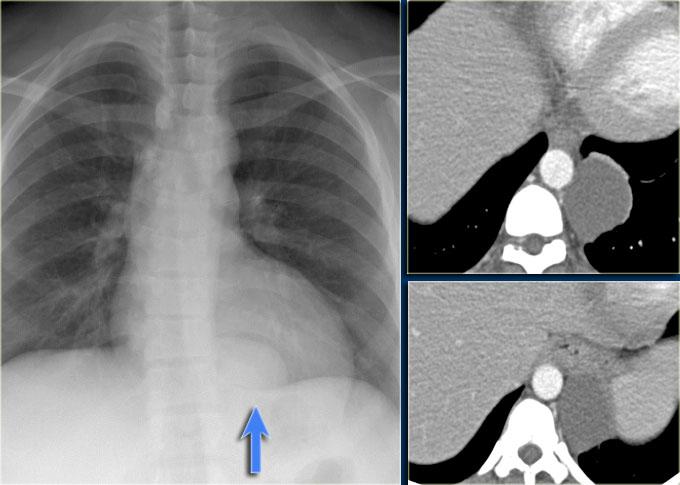

U tuyến ức (Thymoma)

U tuyến ức thường gặp và chiếm 20% các khối u trung thất.

Ung thư biểu mô tuyến ức cực kỳ hiếm gặp và chiếm dưới 1% tổng số các khối u tuyến ức.

Các hình ảnh cho thấy u tuyến ức ở bên trái và ung thư biểu mô ở bên phải.

Ung thư biểu mô tuyến ức đã xâm lấn tĩnh mạch chủ trên (mũi tên).